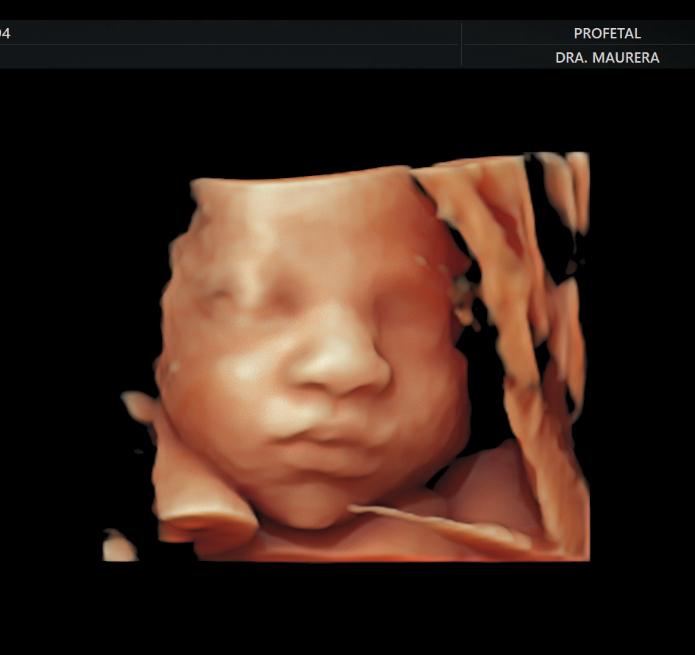

• Ecografía Morfológica Doppler (Semanas 16-26): Un estudio detallado de cada parte del cuerpo fetal (cerebro, corazón, columna, órganos y extremidades) para descartar anomalías estructurales.

• Ecocardiografía Fetal (Semanas 24-28): Un estudio especializado del corazón fetal para descartar cardiopatías congénitas, especialmente en embarazos de alto riesgo.